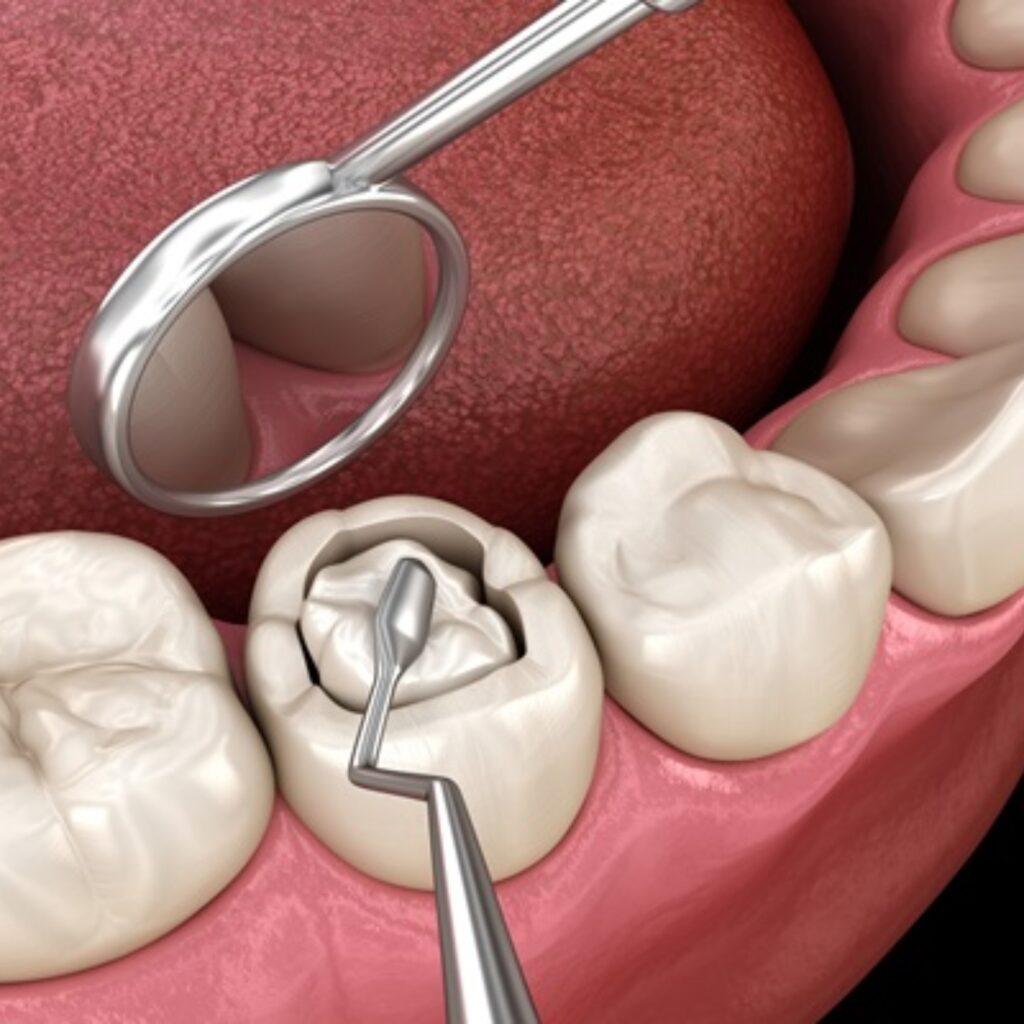

Vijaya Dental Hospital offers advanced dental treatments with modern technology and experienced professionals. It is known for its patient-friendly care, hygiene standards, and high-quality dental services.